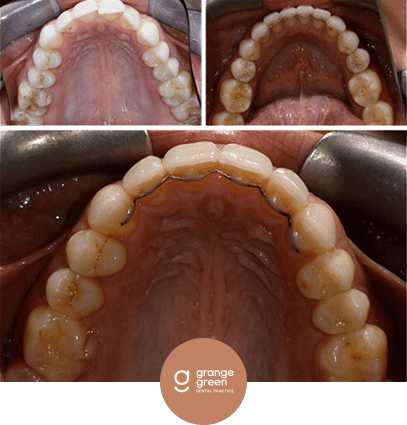

Here are just a few before and after cases to give you an idea of how we help to transform your smile and your confidence using treatments like orthodontics, bridges, veneers and composite fillings…